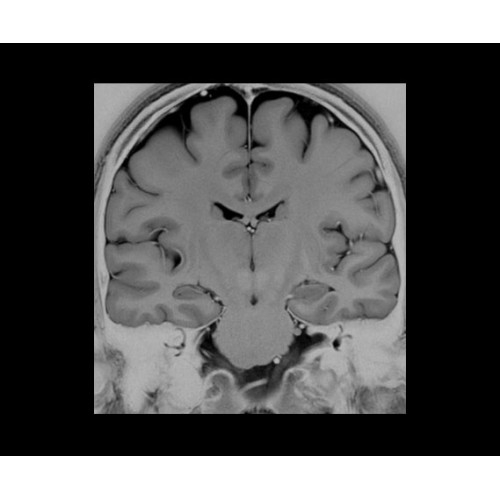

SIGNA PET/MR 3.0T — это гибридная система, в которой совмещаются две принципиально разные технологии — магнитно-резонансную томографию (МРТ) и позитронно-эмиссионную томографию (ПЭТ). Система отличающийся высокой чувствительностью и эффективностью и предназначена для диагностики в области онкологии, неврологии, кардио-васкулярных исследований, исследований воспалительных процессов.

Компания GE Healthcare представляет революционную, полностью интегрированную систему SIGNA PET/MR1, в которой сочетаются времяпролетная технология (TOF) и возможности напряженности магнитного поля 3.0 Тл. Мы поможем вам поднять исследования на более высокий уровень. SIGNA PET/MR позволяет достичь впечатляющей точности и скорости исследований, а благодаря новейшей технологии реконструкции Q.Clear2 качество изображений улучшается в два раза. Кроме того, в систему включен полный набор клинических приложений и гибких катушек для проведения любых видов исследования, открывая для вас возможности визуализации, о которых вы даже не догадывались.

• Специальный пакет приложений для измерения и сравнения объемных изображений ЦНС с нормами поможет вам в диагностике нейродегенеративных заболеваний, а дополнительные инструменты визуализации — в постановке точного диагноза с помощью бета-амилоидов и радиоизотопных маркеров ФДГ.